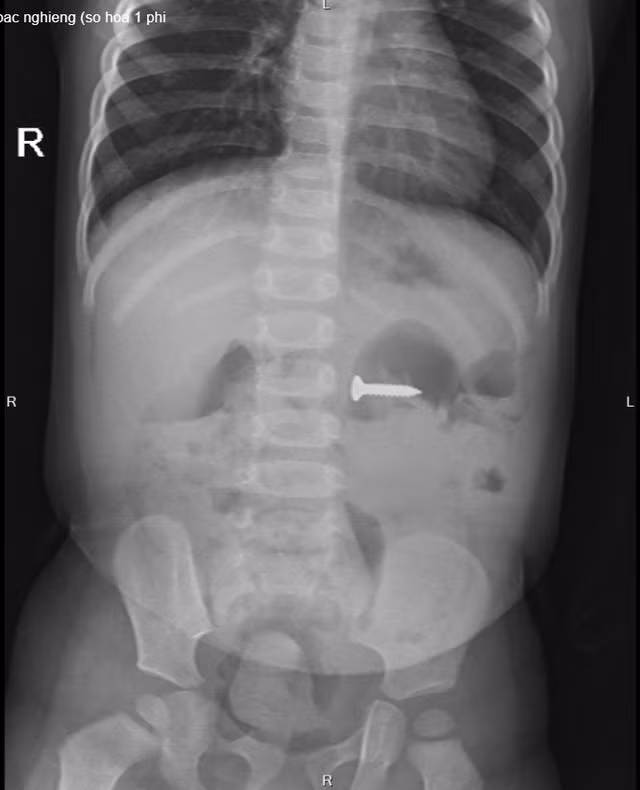

| Chiếc đinh vít sắc nhọn nằm trong dạ dày bệnh nhi trên phim chụp X-quang |

Tại Bệnh viện Sản Nhi tỉnh Phú Thọ, bé C. được chỉ định chụp X-quang thăm dò và phát hiện dị vật đinh vít sắc nhọn kích thước 2 cm trong dạ dày, vị trí ngang đốt sống D3 của trẻ. Sau khi hội chẩn, các bác sĩ Khoa Ngoại nhi tổng hợp đã chỉ định gây mê nội soi tiêu hóa cấp cứu gắp dị vật.